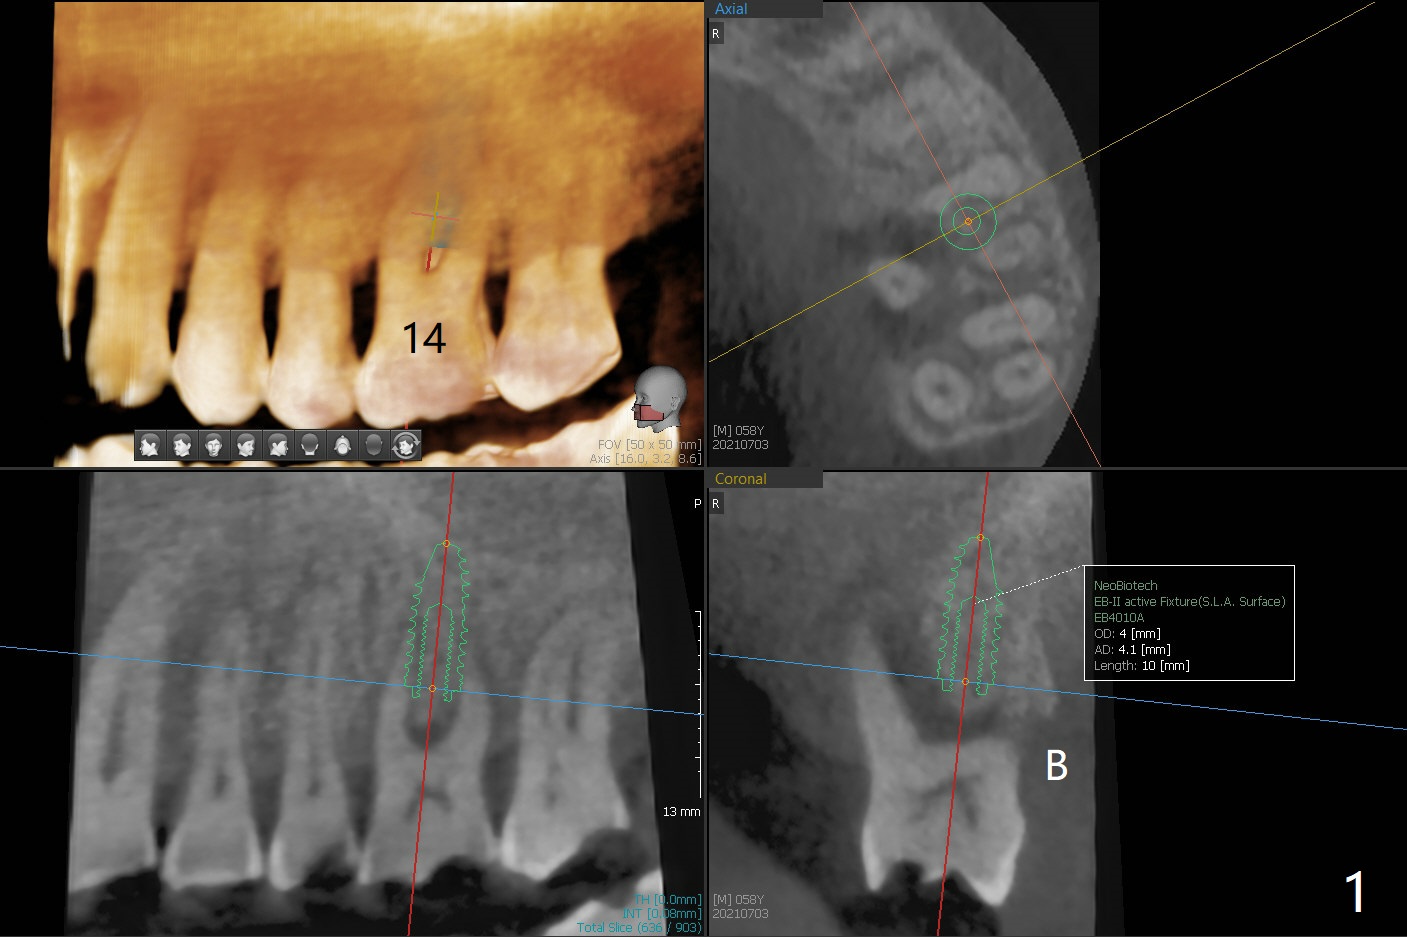

腭侧骨质吸收:颊侧植入

58岁男要求治疗14号牙,吃饭剧痛,CT检查显示腭侧(P)骨质吸收,所以颊侧植入较小植体(图一),13号牙腭侧牙尖折裂(图二),需要牙冠修复。